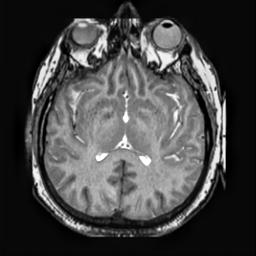

To demonstrate the effectiveness and efficiency of the proposed image fusion method , we conduct a set of comparative experiments on three image datasets. The first is composed by 8 pairs of multi-modal medical images and the second one contains 15 pairs of multi-focus gray or color natural images. These two datasets are often used in many related papers and some examples are shown in Figure 3(a) and Figure 3(b). The third one is a new multi-focus cervical cell image dataset collected by ourselves, which consists of 15 groups of color images and each group contains a series of multi-focus cervix cell images with size of or , etc. Some source examples are shown in Figure 3(c). Our source code implemented in C++ along with the new multi-focus cervical cell image dataset is available online.

We first evaluate the performance of the proposed method under varying total number of octaves and number of layers sampled per octave. The fused images of a pair of multi-modal medical images with different and are shown in Figure 4. In this example, on the one hand, when only 1 or 2 octaves are involved in constructing the DoG pyramid, the fused images fail to keep the integrity information of large size objects (e.g. eyeballs), while by increasing the value of , the integrity information of eyeballs is preserved. On the other hand, although not as significant as the increase of octave numbers , the fused image can contain more details by the increase of layer numbers . The corresponding objective quality metrics are shown in Figure 5. As shown in Figure 5(a), most of the metric values are improved as the number of octaves increases with the fixed layer numbers 3 in the global tendency and each of them tends to be stable when the number of octaves is 5. To get a relatively good quality from Figure 5(b), we can notice that some of the metric values can get a good performance when the number of layers is 3, such as the MI, SSIM, QI and VIF, though there are only a little change of all the metric values by increasing the number of layers with the fixed octave numbers 5. Because it will result in more computation burden with the increase of the value and , and for different kinds of source images, there are different performance with the diverse parameter settings. To get a trade-off between them in our experiments, we set for the multi-modal dataset, for the natural datasets and for the multi-focus cell dataset, respectively.

Figure 6 shows the fused images obtained by different methods with the multi-modal source images shown in Figure 3(a). As shown in these figures, the proposed method can produce images which preserve the complementary information of different source images well. Moreover, due to the scale-invariant structure saliency selection, our method can keep the integrity information of large size objects and the visual details simultaneously. Although the fused image generated by other methods can also capture the details to some extent, all of them fail to keep the integrity information of large size objects such as the eyeballs. Furthermore, from Figure 6(k)-6(t), the DTCWT, GFF, IM and NSCT methods may decrease the brightness and contrast while the proposed method can preserve these features and details without producing visible artifacts and brightness distortions.